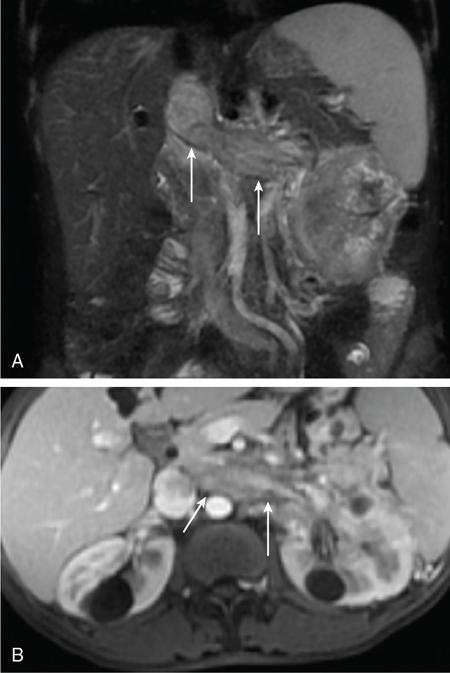

IMAGING OF RENAL MALIGNANCIES IN ADULTS Aparna Katdare, Palak Bhavesh Popat, Nilesh P. Sable, Ganesh Bakshi, Suyash Kulkarni Detection of renal masses has increased remarkably in recent times owing to wide-spread use of cross-sectional imaging. Imaging plays an important role in characterizing renal masses and is indispensable in treatment planning in renal malignancies. The most commonly encountered malignant renal masses in practice include renal cell carcinoma (RCC), urothelial carcinoma, lymphoma and metastases. Urothelial carcinoma and lymphoma have been covered in detail in separate chapters. RCC constitutes nearly 90% of all renal malignancies with a higher incidence in North America and Europe than India, Africa and China. With an increase in the number of cross-sectional studies performed, especially in Western population, the incidental diagnosis of RCC has increased in recent times, with such incidentally diagnosed lesions presenting at earlier stages with better prognosis and reduced rates of recurrence. The median age of presentation of RCC is 64 years according to the Surveillance, Epidemiology and End Results (SEER) program database and almost a decade earlier in Indian population, with a definite increasing risk of RCC with increasing age. Males are affected about 2–3.5 times more than females. In the Indian population, patients have been seen to present at a later stage as compared to the Western population. Amongst the various postulated risk factors, there is convincing evidence that smoking, hypertension, obesity and acquired renal cystic disease increase the risk of RCC. Alcohol intake and physical activity have been found to be associated with reduced risk of RCC. Trichloroethylene and cadmium exposure have been postulated as likely causes as well. Two to four per cent of RCCs are hereditary, with association of various genetic disorders such as Von Hippel Lindau (VHL) syndrome, hereditary papillary renal carcinoma, hereditary leiomyomatosis RCC, Birt-Hogg-Dube syndrome, chromosome 3 translocation and tuberous sclerosis (TCS1, TCS2). The WHO classification of 2016 (Table 11.25.1.1) stratifies tumours of the kidney into different subtypes based on cytoplasmic and architectural features, tumour location, background renal disease and molecular alterations. Clear cell renal cell carcinoma Multilocular cystic renal neoplasm of low malignant potential Papillary renal cell carcinoma Hereditary leiomyomatosis and renal cell carcinoma-associated renal cell carcinoma Chromophobe renal cell carcinoma Collecting duct carcinoma Renal medullary carcinoma MiT family translocation renal cell carcinomas Succinate dehydrogenase-deficient renal carcinoma Mucinous tubular and spindle cell carcinoma Tubulocystic renal cell carcinoma Acquired cystic disease-associated renal cell carcinoma Clear cell papillary renal cell carcinoma Renal cell carcinoma, unclassified Papillary adenoma Oncocytoma 8310/3 8316/1a 8260/3 8311/3* 8317/3 8319/3 8510/3a 8311/3a 8311/3 8480/3a 8316/3a 8316/3 8323/1 8312/3 8260/0 8290/0 Metanephric adenoma Metanephric adenofibroma Metanephric stromal tumour 8325/0 9013/0 8935/1 Nephrogenic rests Nephroblastoma Cystic partially differentiated nephroblastoma Paediatric cystic nephroma 8960/3 8959/1 8959/0 Clear cell sarcoma Rhabdoid tumour Congenital mesoblastic nephroma Ossifying renal tumour of infancy 8964/3 8963/3 8960/1 8967/0 Leiomyosarcoma Angiosarcoma Rhabdomyosarcoma Osteosarcoma Synovial sarcoma Ewing sarcoma Angiomyolipoma Epithelioid angiomyolipoma Leiomyoma Haemangioma Lymphangioma Haemangioblastoma Juxtaglomerular cell tumour Renomedullary interstitial cell tumour Schwannoma Solitary fibrous tumour 8890/3 9120/3 8900/3 9180/3 9040/3 9364/3 8860/0 8860/1a 8890/0 9120/0 9170/0 9161/1 8361/0 8966/0 9560/0 8815/1 Cystic nephroma Mixed epithelial and stromal tumour 8959/0 8959/0 Well-differentiated neuroendocrine tumour Large cell neuroendocrine carcinoma Small cell neuroendocrine carcinoma Phaeochromocytoma 8240/3 8013/3 8041/3 8700/0 Renal haematopoietic neoplasms Germ cell tumours The morphology codes are from the International Classification of Diseases for Oncology (ICD-O) {917A}, Behaviour is coded/0 for benign tumours; /1 for unspecified, borderline or uncertain behaviour; /2 for carcinoma in situ and grade III intraepithelial neoplasia; and /3 for malignant tumours. The classification is modified from the previous WHO classification (756A), taking into account changes in our understanding of these lesions. aNew code approved by the IARC/WHO Committee for ICD-O. Of these, the most common entity is the clear cell subtype, while papillary and chromophobe subtypes are less common. The different subtypes show varied biological behaviour, treatment response and prognosis. The 2017 guidelines by American Urological Association (AUA) as well as 2019 guidelines by European Society of Medical Oncology (ESMO) recommend multiphase cross-sectional imaging by either CT or MRI for renal mass characterization and staging. AUA 2017 guidelines recommend renal mass characterization on the basis of tumour complexity, contrast enhancement and presence or absence of fat. MRI has an upper hand over CT in characterizing subtle mass enhancement, cystic lesions and lesions less than 2 cm. ESMO recommends contrast-enhanced CT study of the chest, abdomen and pelvis for renal mass staging. Bone scan and brain CT or MRI can be considered if indicated by clinical or laboratory investigations. For characterization of renal masses, a multiphase CT or MRI study is recommended. CT study constitutes an unenhanced study followed by contrast injection and acquisition of corticomedullary phase at 40 seconds, nephrographic phase at around 100 seconds and delayed phase at around 5 minutes. MRI protocol includes T2-weighted single-shot fast spin-echo 2D sequences, axial T1-weighted 2D sequence with in-phase and opposed-phase gradient echo imaging, precontrast and postcontrast imaging with a 3D T1-weighted spoiled gradient recalled sequences in corticomedullary phase at 30 seconds, nephrographic phase at 100 seconds, 180–210 seconds and delayed phase imaging at 5 minutes and diffusion-weighted imaging with multiple b-values 0–50, 400–500 and 800–1000 s/mm2. The ACR White Paper on CT imaging of incidental renal mass recommends using the following descriptors for characterizing renal masses: Given the prognostic implications, it is worthwhile for radiologists to know the imaging features that may help discriminate between the common histological subtypes of RCC on various imaging modalities. This is the most common histological type of RCC, accounting for about 70% of cases. These are exophytic tumours with a heterogeneous appearance due to the presence of necrosis, intratumoural haemorrhage, cystic components with septations and calcific foci and hence have a more heterogeneous appearance on cross-sectional imaging than the other subtypes (Fig. 11.25.1.1). Necrosis is seen more often in larger masses and higher tumour grades (Fig. 11.25.1.2). On CT, depending on the tumour composition, these are seen as heterogeneous lesions, show marked contrast enhancement in the corticomedullary phase with washout on nephrogenic phase (Fig. 11.25.1.2). On MRI, these characteristically show high signal intensity on T2W sequences (Fig. 11.25.1.3). The presence of intracytoplasmic fat in the clear cells of the tumour is reflected in the loss of signal in opposed phase images on chemical shift imaging, which is seen in nearly 60% of these tumours. A pseudocapsule may be seen, which is best appreciated on T2-weighted imaging on MRI; the presence of a pseudocapsule has a high negative predictive value for perinephric extension (Figs. 11.25.1.3 and 11.25.1.4). Conversely, larger tumours with higher grades often have interrupted pseudocapsule and hence tend to be irregular, spread into the perinephric fat with renal vein and inferior vena cava (IVC) invasion (Figs. 11.25.1.5 and 11.25.1.6). On diffusion-weighted imaging, clear cell RCCs have been seen to have higher ADC values than nonclear cell RCCs, and lower-grade tumours have been seen to have higher ADC values than higher-grade tumours. The clear cell variant has worse prognosis than the papillary and chromophobe subtypes, presenting at a more advanced stage and being more likely to recur or metastasize (Fig. 11.25.1.7), with lower 5-year survival rates at 44%–69% as compared to 78%–92% for the other two. Papillary RCC comprises about 10%–15% of RCCs. These are slow-growing tumours and hence are well-marginated in contrast to clear cell RCC. As they are hypovascular, their enhancement on CT is significantly less than clear cell RCC (Fig. 11.25.1.8). These show characteristically low signal on T2W images on MRI (Fig. 11.25.1.9). Intracytoplasmic or macroscopic fat is less often seen on MRI imaging as compared to the clear cell variants. Larger tumours tend to be more heterogeneous (Fig. 11.25.1.10). These tumours may sometimes show cystic appearances, mural projections or blood degradation products. Calcifications are more common in papillary variants than clear cell RCC. Multifocality and bilaterality are also more common in these tumours than clear cell variants. These account for about 5% of RCCs. These are less aggressive, more homogeneous and hypovascular lesions than clear cell variants, with intensity of contrast enhancement on cross-sectional imaging being midway between clear cell and papillary variants. They show low to intermediate T2 signals on MRI. A characteristic feature is the presence of a central scar and spoke-wheel enhancement, the latter being a histopathological and imaging similarity between these tumours and oncocytoma (Fig. 11.25.1.11). Other subtypes of RCC are much less common but some may show distinct imaging findings. Multilocular cystic RCCs have excellent prognosis and lack mural nodules within the cystic components, unlike clear cell RCCs with cystic degeneration which show mural nodules. Collecting duct carcinomas, on the other hand, are aggressive tumours with poor prognosis and have medullary origin, and therefore appear similar to transitional cell carcinomas on imaging. Medullary RCCs are associated with sickle cell disease and sickle cell trait and are seen as infiltrating intracalyceal obstructive lesions with associated nodal disease. The imaging work-up of a suspected RCC is aimed at: Localized renal cancer is defined as a disease confined to the renal capsule and refers mainly to stage I and II disease. Nearly 70% of RCCs, especially the lower-stage lesions, are incidentally diagnosed on cross-sectional imaging. Also, amongst incidentally diagnosed renal lesions less than 4 cm in size, about 20% turn out to be benign on histopathology. Asymptomatic incidentally diagnosed small renal masses have an indolent course and better prognosis. Nephron-sparing surgery (NSS) has gathered momentum in recent years due to promising results and prognoses in small lesions. The 2017 AUA guidelines for localized renal masses describe restricted and well-defined indications for radical nephrectomy, bigger role of nephron-sparing procedures such as partial nephrectomy, tumour enucleation and thermal ablation, as well as increasing role for biopsy as well as active surveillance of such lesions. Hence, imaging findings in these lesions become critical in charting management of these patients. The imaging features of common histopathological subtypes of RCCs have already been discussed above. Signal intensity on T2W images and corticomedullary phase enhancement have been seen to be independent predictors of clear cell and papillary RCCs. Further, T2 signal homogeneity can be a predictor for slower growth rate. Hence, in general, multiparametric MRI studies have been shown to be effective in small renal mass characterization and can subsequently guide decisions regarding biopsy, surgery or surveillance. CT is a good alternative in patients with contraindication to MRI. For cystic renal lesions, the Bosniak classification, which stratifies the risk of neoplasia in cystic renal lesions based on the complexity of their appearance (wall thickness, septations, solid component), can be used effectively to decide further course of management. The Bosniak classification originally applies to CT findings but can logically be extrapolated to MRI, USG and Contrast Enhanced Ultrasound (CEUS) as well. Bosniak I and II cysts are benign while Bosniak IIF, III and IV cysts show progressively increasing risk of neoplasia. Given the more indolent course of cystic RCCs as compared to solid lesions and possible complications of interventions, lately there has been a case for even the type III and IV cysts, which previously would be operated, to be followed up, especially if patient has existing comorbidities or if the solid component is minimal. Initial follow-up would be at 6 months, followed by annual imaging. AUA 2017 guidelines recommend considering renal mass biopsy if haematologic, metastatic, inflammatory or infectious aetiology is suspected. Once the need for surgery is established in a localized disease, NSS may be considered for stage Ia and Ib disease. To predict perioperative outcomes in NSS, various scoring systems have been proposed for preoperative renal mass evaluation, such as R.E.N.A.L. nephrometry score, PADUA score (Preoperative aspects and dimensions used for anatomical classification), C-index method and mathematical tumour contact surface area (CSA). The popular R.E.N.A.L. nephrometry score takes into account various tumour descriptors that help decide the technical feasibility of NSS and predict surgical outcomes. These include tumour radius, exo/endophytic location, nearness to collecting system or renal sinus, anterior/posterior location and location with reference to polar lines. These descriptors need to be commented upon diligently while reporting renal masses (Table 11.25.1.4). Higher scores are seen to correlate with ischaemia time, postoperative urologic complications, higher grade and mortality. These include organ-confined tumours more than 7 cm in size, or tumours of any size which show regional nodal involvement and/or invasion of perinephric tissues but confined to Gerota’s fascia. These include renal vein and IVC invasion (luminal and mural). Generally, radical nephrectomy is recommended by the National Comprehensive Cancer Network (NCCN) in stage II and III RCCs. Both CT and MRI are effective in diagnosing locally advanced disease in RCC. The loss or interruption of pseudocapsule is seen in more infiltrative and aggressive disease and is best seen on MRI. Local infiltration may be in the form of contiguous spread to perinephric tissues or discrete deposits in perinephric fat (Fig. 11.25.1.15). IVC or renal vein invasion could be in the form of intraluminal thrombosis or invasion of the vessel wall and have implications on surgical approach and outcomes. Tumour thrombus can be distinguished from bland thrombus by confirming vascularity within the thrombus on imaging. Doppler evaluation, CEUS, CT and MRI can all be helpful for the same. MRI is better than other modalities for venous evaluation, especially for mural invasion and IVC invasion (Figs. 11.25.1.16 and 11.25.1.17). Right-sided tumours, anteroposterior IVC diameter of 2.4 cm or more at the level of renal hilum and complete IVC occlusion at this level are associated with higher risk of IVC resection. About 16% of patients with RCC have metastases at diagnosis and about 20%–30% of patients operated for local disease develop recurrence or metastases at a later date. The recurrent disease occurs most commonly within 3 years of diagnosis and uncommonly even later in young patients or large tumours. The most common sites of metastases from RCC are lungs, liver, bones, nodes, adrenals and brain. CT scan is the preferred modality for primary staging and surveillance for metastases because of its widespread availability and versatility for diagnosing bone and soft tissue lesions. MRI is preferred for looking for recurrence in postablative lesions, wherein these are seen as new enhancing lesions or show increase in the size of preexisting enhancing components. 18FFluorodeoxyglucose – Positron Emission Tomography (PET)/CT and PET/MRI may be helpful to look for metastatic disease as well. 18FSodium fluoride – PET/CT has been found to be better than CT and bone scan in detecting osseous metastases. RCC is a relatively radiation-resistant tumour, and treatment options tilt in favour of surgical procedures for localized and locally advanced diseases. For metastatic disease, post-risk assignment, the treatment has to be planned. Treatment can be offered as per size and the clinical stage.